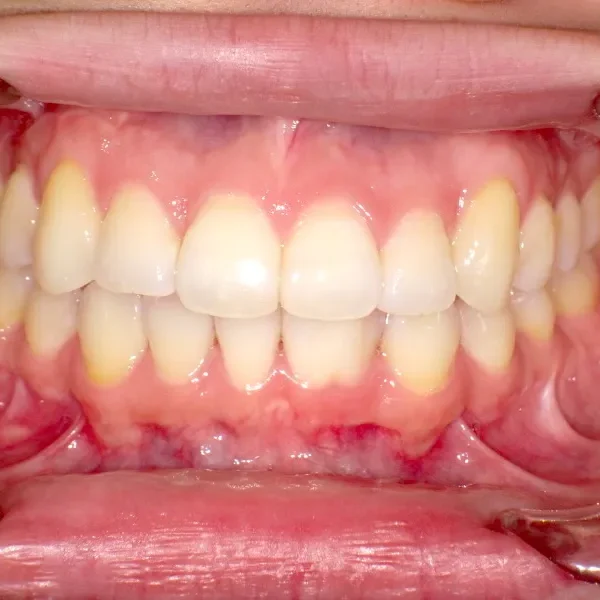

治療終了後

八重歯で笑うと尖った歯が目立ちます。

上下ガタガタで、下の歯は癒合歯(2本がくっついて1本の歯)です。

治療回数71回、3年5ヶ月の治療期間で矯正治療を終了しました。

主訴が改善され、ご満足頂きました。